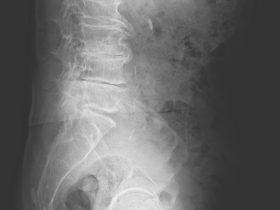

腰が痛いという訴えの中で一番多いのは、いわゆる「腰痛症」ですが、腰椎椎間板ヘルニアによる痛みはおよそ20~30%を占めています。 -

「腰椎椎間板症の症状、治療及び治療期間と安静期間」 腰椎椎間板症とは、腰痛を引き起こす可能性のある3つの変性疾患を指します。 その3つは主に椎間板内破壊、椎間板変性、椎間関節不安定性です。 症状には、6… -

腰椎椎間板症が治らない原因と狭い椎間板を改善する方法